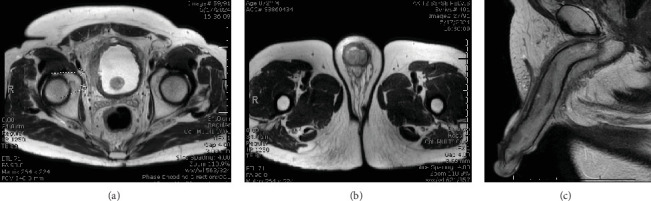

恶性阴茎勃起症继发于泌尿生殖系统恶性肿瘤是一种罕见的晚期肿瘤发现。一名72岁男性,既往有肌肉浸润性膀胱癌病史,曾接受三模式治疗,表现为精神状态改变,Foley导尿管排出白色分泌物,双侧身体僵硬。最初的盆腔磁共振成像显示下体肿胀,无明显肿瘤侵袭。患者最终接受了阴茎探查和双侧减压,活检显示高度尿路上皮癌侵犯了下体组织。尽管目前的指导方针阴茎勃起,我们提出了一个三层的方法来管理恶性阴茎勃起。

Malignant priapism secondary to a genitourinary malignancy is a rare and late-stage oncological finding. A 72-year-old man with a past medical history of muscle-invasive bladder cancer treated with trimodal therapy presented with altered mental status, white discharge from his Foley catheter, and bilateral corporal rigidity. Initial pelvic magnetic resonance imaging demonstrated engorgement of the corporal bodies without obvious tumor invasion. The patient eventually underwent penile exploration and bilateral decompression, and a biopsy revealed high-grade urothelial carcinoma invading the corporal tissues. Despite current guidelines for priapism, we present a three-tiered approach to the management of malignant priapism.